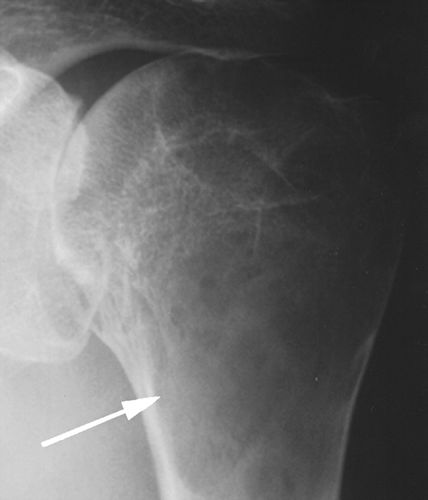

图13A-51岁男性,类风湿性关节炎。射线照片显示肱骨近端的大的病变(箭头)延伸到关节面,类似巨细胞瘤。盂肱关节间隙缩小。对侧肩部的射线照片显示了类似的发现。滑膜囊肿很少达到这样大小并模仿肿瘤。

图13B-51岁男性,类风湿性关节炎。手的X线片显示类风湿性关节炎的典型表现,包括涉及多个关节的狭窄和侵蚀。注意第三和第四近端指间关节附近的软组织肿胀和第二掌指关节的强直。